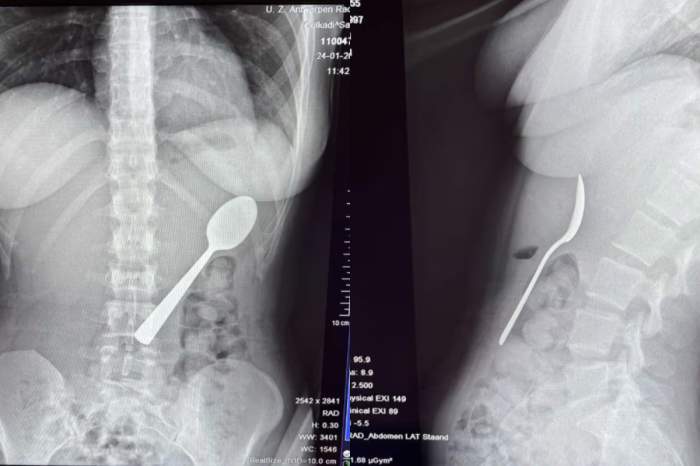

O femeie a înghițit accidental o lingură lungă de 17 cm când câinele ei a sărit în poala ei în timp ce mânca iaurt. Reymy Amelinckx a spus că a trebuit să aleagă între „a se sufoca sau a înghiți lingura”, deoarece a simțit cum tacâmul „aluneca ușor în stomac”.

Tinerei i-au scos lingura din stomac două zile mai târziu

Ustensila i-a fost îndepărtată sub anestezie locală, fără să fie nevoie de o intervenție chirurgicală deschisă.

Câteva ore mai târziu după intervenție, tânăra a fost externată și a început să se recupereze rapid. Spune că a avut unele dureri în gât din cauza leziunilor esofagului, câteva episoade minore de sângerare gastrică și stomacul sensibil pentru o perioadă, însă nu a avut leziuni permanente.